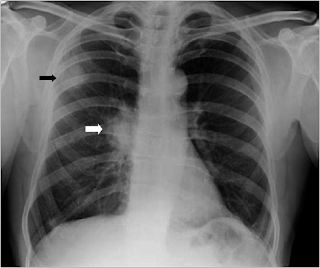

Lung cancer Is Rarely Detected By Current X-ray Procedures

Lung cancer is rarely detected by current X-ray procedures 25 August 2014 Joanna Kristiansen (from left), Trond Mogens Aaløkken and Anne Catrine Trægde Martinsen have developed a ... Access Full Source